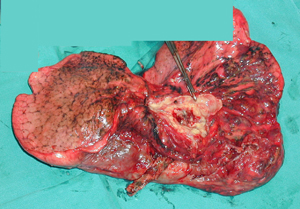

Εικόνα 3

Το χειρουργικό παρασκεύασμα, που είναι ολόκληρος ο πνεύμονοςς με τον όγκο να διακρίνεται κεντρικά. Η ιστολογική εξέταση έδειξε ότι πρόκειται για πλακώδες καρκίνωμα που αποτελεί τον συχνότερο ιστολογικό τύπο.